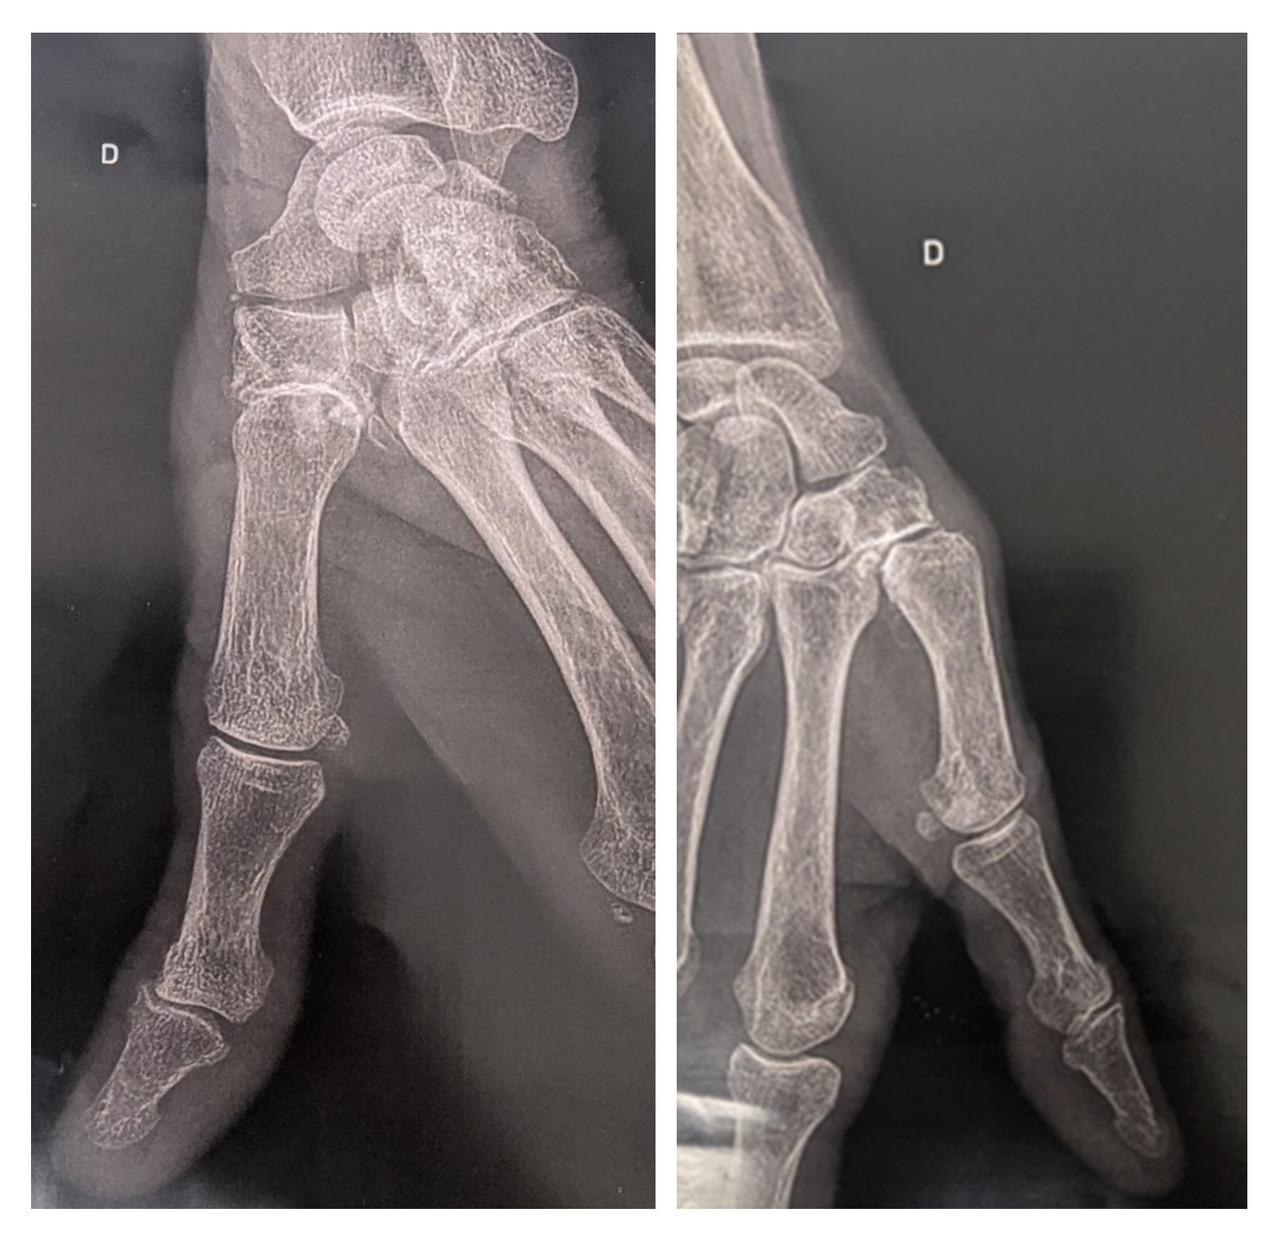

Le bilan radiographique permet de confirmer le diagnostic de rhizarthrose. Il est nécessaire de demander des incidences radiographiques du pouce de face et de profil selon Kapandji. Décrites en 1980 par Kapandji et al.,2 elles sont spécifiquement centrées sur l’articu­lation trapézo-métacarpienne et permettent de visualiser précisément l’inter­ligne articulaire, contrairement aux radiographies standards de la main. Les principaux signes radiologiques de rhizarthrose sont les suivants (fig. 3) :

• pincement articulaire ;

• présence d’ostéophytes du trapèze ;

• existence d’une subluxation latérale du métacarpien.

Les radiographies de face et de profil du pouce selon les incidences de Kapandji permettent de confirmer le diagnostic.